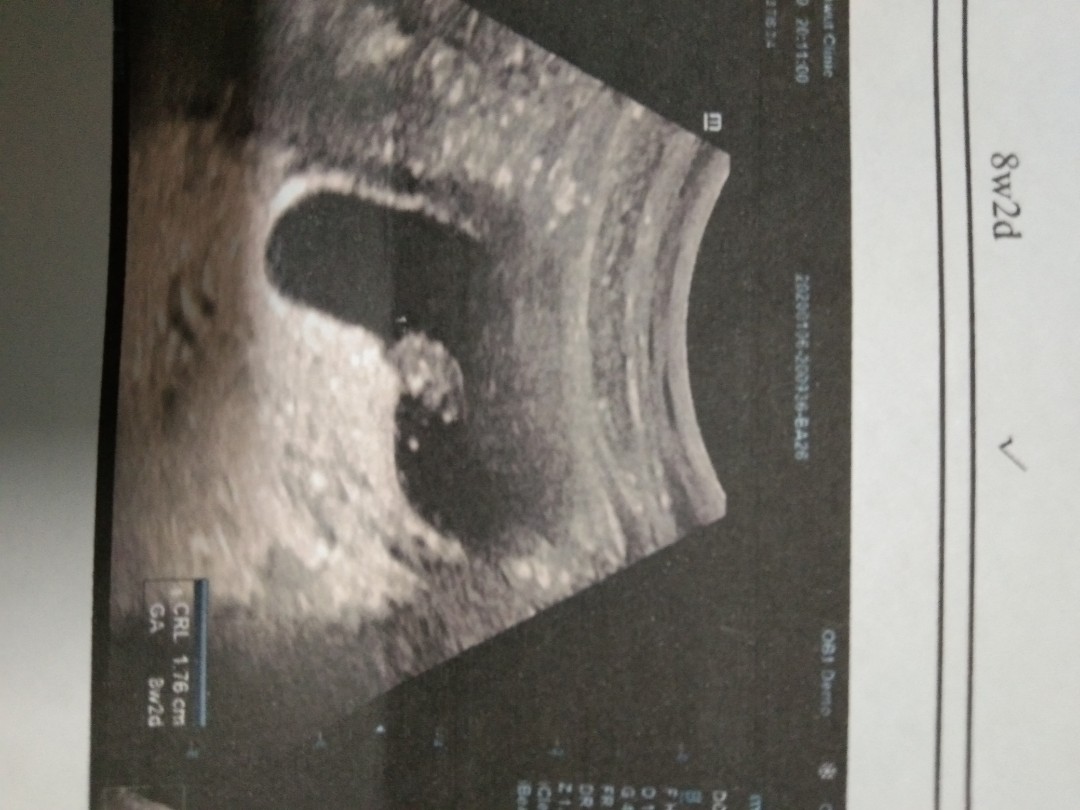

ซาวตอน8w2d ทีมสิงหาจ้า